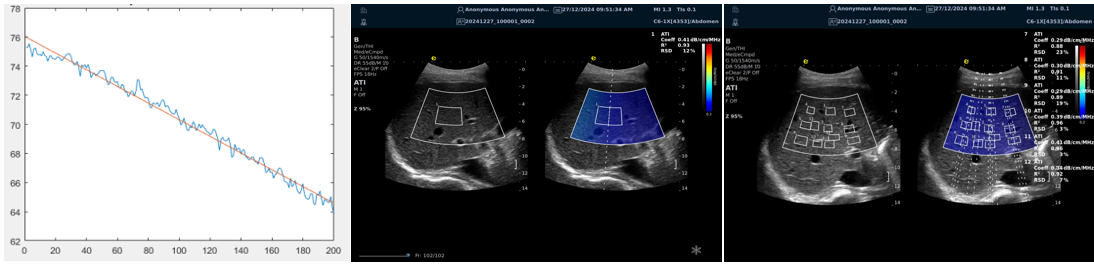

ATI高级声衰减成像

?独有的幅度损失的衰减方法ALA,准确性高,稳定性好,实时性好?业界唯一支持凸阵与线阵两种探头?支持多个取样框?提供两种显示单位

1b93bd09b343ed7a1e0b155407e34f4.png

肌骨领域的应用

?肌腱炎症或损伤的评估?肌肉拉伤的定位?关节磨损或炎症的诊断?骨质疏松的早期发现和监测